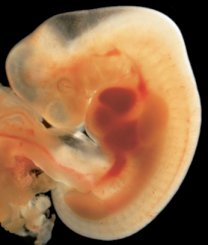

And the photograph below is a textbook photo so you can see the detail: